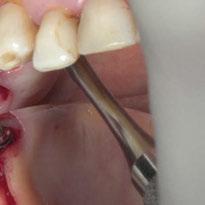

Para ilustrar el proceso, presentamos el caso de una mujer joven diagnosticada de carcinoma adenoide quístico en la región posterior del hemipaladar izquierdo (Figuras 1 y 2). El procedimiento quirúrgico realizado fue una

maxilectomía parcial que incluyó las piezas 24-26 y desde el reborde alveolar hasta la base del cráneo (Figuras 3 y 4). En este caso, la órbita y el globo ocular pudieron ser preservados. La reconstrucción inmediata se realizó mediante un colgajo de músculo temporal homolateral (Figura 5) y el defecto de la fosa temporal fue cubierto mediante una malla de titanio. Posteriormente, la paciente recibió radioterapia (Figuras 6 y 7). 2 años más tarde se diseñó un IS con anclaje en el arbotante nasomaxilar, zona subnasal izquierda

Figura 1. Imagen preoperatoria de la paciente.

Figura 2. Carcinoma adenoide quístico en región posterior del hemimaxilar izquierdo.

Figura 3. Maxilectomía parcial.

Figura 4. Defecto maxilar tras resección del tumor.